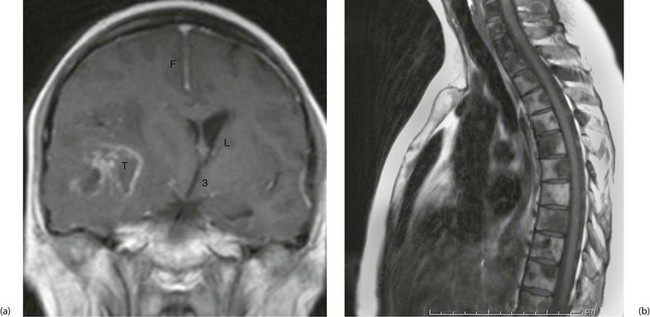

Principles of radionuclide scanning

Radionuclide or isotope scanning is the application of nuclear medicine for diagnosis, by identifying sites of abnormal physiology, e.g. the presence of pus, abnormal phagocytic activity or areas of excessive bone turnover. Isotope scanning, however, gives poor anatomical detail. Suitable tracer agents combine a substance taken up physiologically by the target tissue and a radioactive label, usually technetium-99m (99mTc).

The tracer is concentrated in a specific type of tissue (such as iodine in the thyroid) or else in tissues with similar physiological or pathological activity such as reticulo-endothelial cells or areas of inflammation.

A gamma camera consisting of multiple detector units collects and counts the level of radioactivity across the area of interest. This produces a complete image in one exposure (see Fig. 5.12). Several views are taken from different directions (usually anterior, posterior and oblique).

Fig. 5.12 Isotope scanning using a gamma camera

The patient has received an intravenous injection of radiolabelled tracer. The pattern of uptake is imaged by the detector array and transmitted electronically to be displayed on a monitor

Some pathophysiological functions can be investigated by dynamic imaging. For this, detection of isotope continues over a period and the changing level of radioactivity is recorded for later analysis. Examples of this include estimating renal blood flow and studying renal clearance.